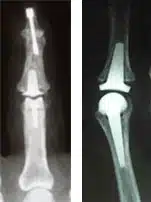

Für die Fingergrundgelenke ist der prothetische Gelenkersatz das Mittel erster Wahl, bei den Fingermittelgelenken, je nach Beanspruchung der Hände, prothetischer Gelenkersatz oder aber Versteifung der Gelenke.

Bei den Endgelenken ist stets die Versteifung und Achskorrektur indiziert, da dadurch nur ein Verlust der Gesamtbeweglichkeit des Fingers von 10% eintritt.